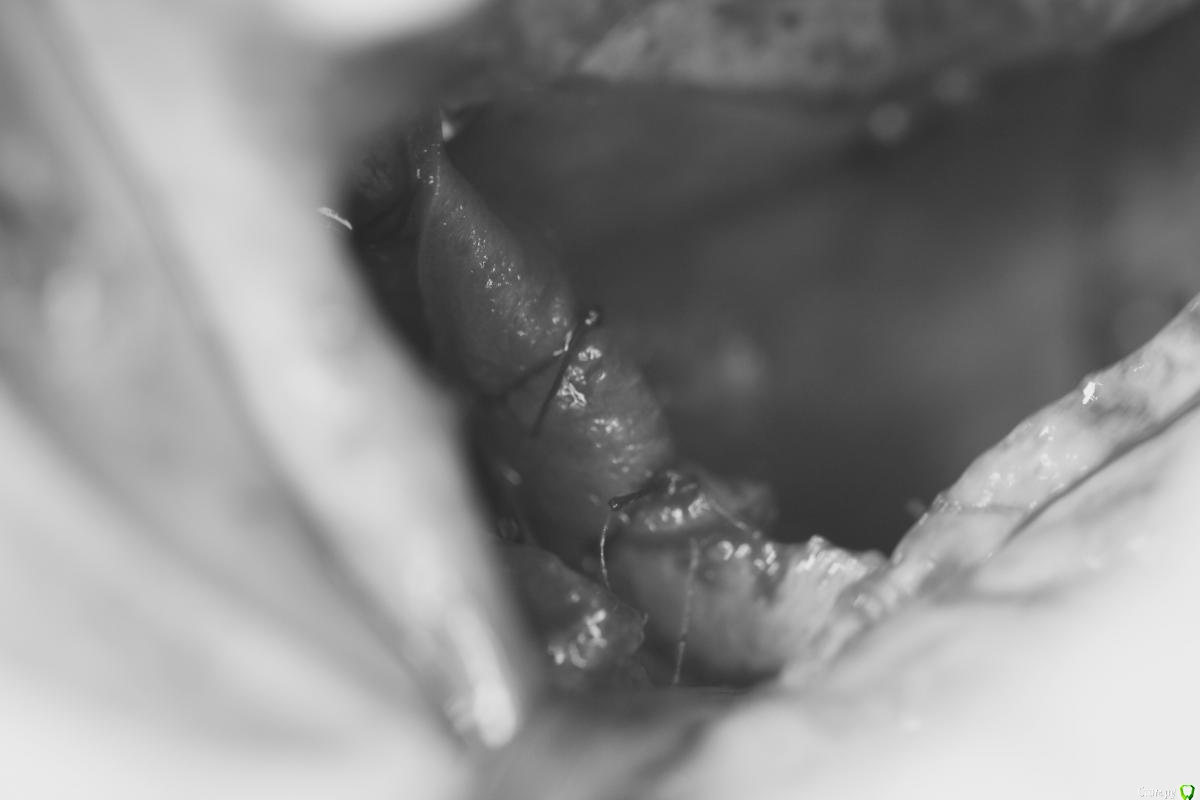

Zorrro Опубликовано 17 января, 2017 Поделиться Опубликовано 17 января, 2017 (изменено) У меня была похожая в чём-то ситуация,когда создалось впечатление мнимого благополучия.Сейчас скину скан кт. Что меня больше всего сбило с толку,так это абсолютно ровный наружный контур аугментатаи не воспалённая мембрана синуса… Изменено 17 января, 2017 пользователем Zorrro 4 Ссылка на комментарий

Zorrro Опубликовано 17 января, 2017 Поделиться Опубликовано 17 января, 2017 Чем закончилось?Повторным синусом,если можно это так назвать.Изначально у пациентки была очень тонкая костная стенка ,местами не заросшая после удалениятак что после неудачного первого синуса получил довольно большой дефект.Ситуация доЧерез 6 месПосле удаления каши из синуса,решил подстраховаться и выстелил дно мембраной,припинив её к небной стенке изнутри и к латеральной стенке снаружи.Потом титановая сетка,которую перекрыл коллагеновой мембранойПерекрестил и ушил.ждём … 1 Ссылка на комментарий